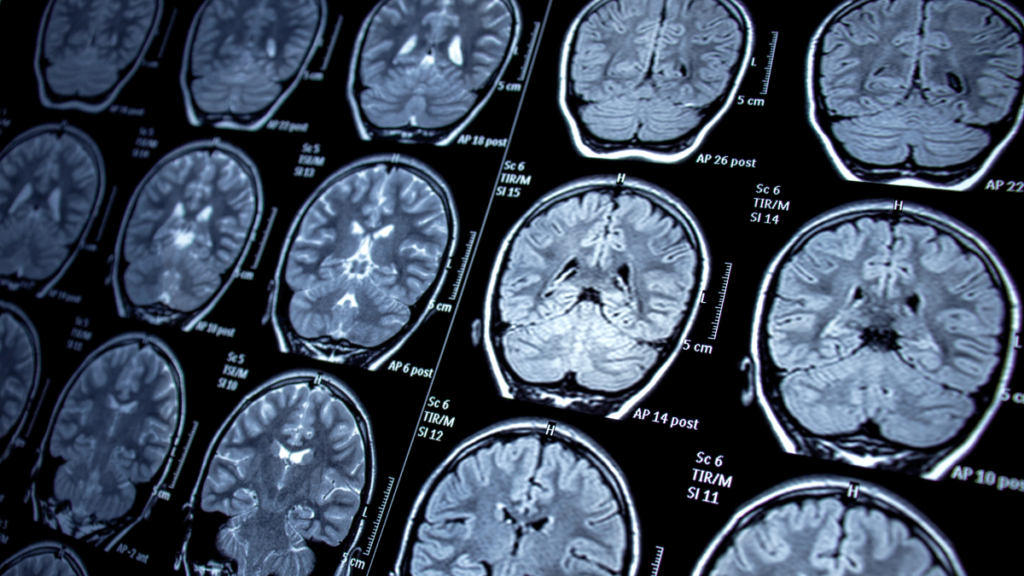

É fundamental trazer todos os exames realizados anteriormente (imagens de ressonância em CD/Link e laudos, exames de sangue e líquor). Também recomendamos anotar todas as suas dúvidas e os medicamentos que está utilizando no momento.

Esclerose Múltipla

Diagnóstico diferencial e tratamentos modificadores da doença para preservar a funcionalidade.

NMO

Cuidado específico para espectro NMOSD, focado na prevenção de surtos e controle inflamatório.